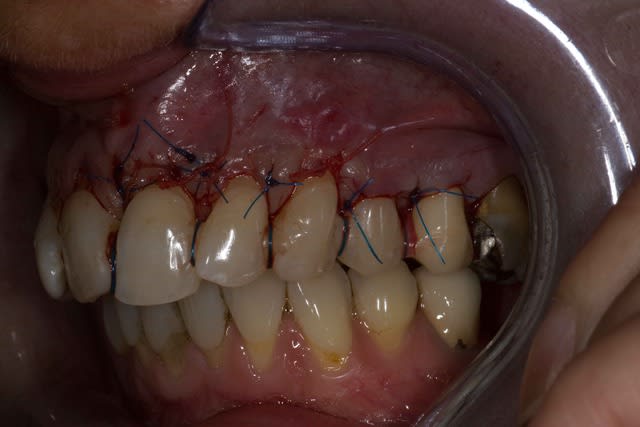

Img 2078 jexjqo - Eugenol

Img 2079 zq4nhx - Eugenol

Img 2076 afcxn3 - Eugenol

tillcky luke : l'homme qui dégaine son scalpel plus vite que son ombre.

Sympa de poster ton boulot ;)

Effectivement David tu ne pouvais pas mettre en application de façon plus rapide.

Merci de poster ce cas et ta chirurgie même si tu sais ce que je pense de la technique de tunnélisation ;-))

Oui effectivement et la j'ai trouvé la limite de cette technique j'ai pas bien réussi a tracter mon lambeau :/.

Je pense qu'a partir de maintenant je vais me mettre au LDC histoire de me faire vraiment la main avec cette technique.